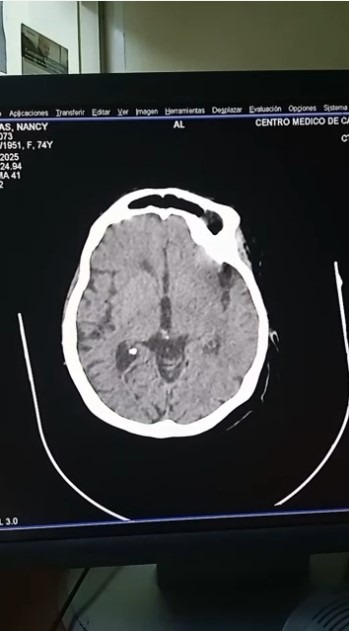

Ischemic stroke (CVA) with left-side weakness.

Accidente cerebrovascular (ACV) isquémico, con hemiparesia en el lado izquierdo.